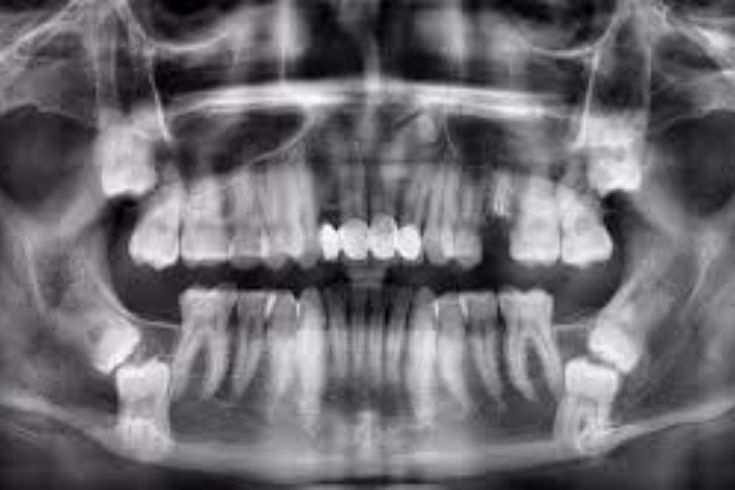

Cách xử lý: Đừng chần chừ, hãy quay lại nha khoa để tái khám. Bác sĩ sẽ tiến hành chụp phim X-quang để kiểm tra kỹ lưỡng bên trong xương hàm, từ đó xác định nguyên nhân chính xác và đưa ra phương án điều trị phù hợp.